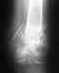

Re: вывих акромиального соединения ключицы

Насчет "лучше лавсана еще ничего не придумано" - это спорный тезис.

В свежем случае (до 2 нед.) можно лишь удержать ключицу во вправленном состоянии 4-6 нед, связки срастутся. Для этого подойдут разного рода повязки с давящим на ключицу пелотом, либо аппаратик внешней фиксации.

Связки надо восстанавливать (лавсаном или консервированным сухожилием) только в застарелых случаях.

Использование hook plate выгодно тем, что можно не восстанавливать связки и в застарелом случае, пластина держит хорошо. Ограничения движений при этом нет.

У нас сейчас в ходу в основном hook plate без всяких пластик связок (Вы внятно не пишете, где находитесь, если в Н-скее - поищите фирму "Деост"). Раньше в свежих случаях широко пользовались аппаратами (см. презентацию, делалась в Праге на EuroTrauma'2004), можете ее показать местным докторам. Ни hook plate, ни аппарат не требуют гипсовой повязки в принципе. Можно сразу двигать рукой как угодно.